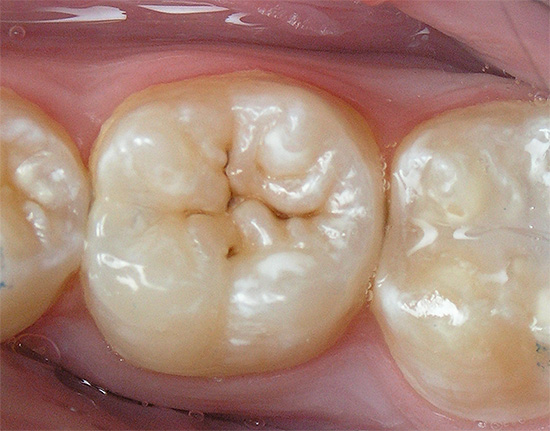

La seguente foto mostra chiaramente che la carie delle fessure è localizzata principalmente nella parte centrale della superficie masticatoria del dente. Se la malattia non è iniziata, la radice e il collo non sono interessati:

Il quadro clinico della nosologia consiste precisamente nella colorazione e nell'ulteriore distruzione dello smalto nell'area della fessura.